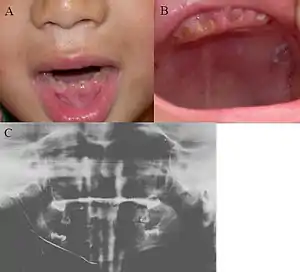

| Oral photographs from an individual with Dentinogenesis imperfecta | |

Clinical appearance is variable with presentation ranging from gray to yellowish brown, but the characteristic feature is the translucent or opalescent hue to the teeth.

Radiographic features

Type I and II have similar radiographic features[6]

- Total obliteration of the pulp chamber and root canals due to deposition of dentine

- Bulbous crowns with apparent cervical constriction

- Reduced root-length with rounded apices

Type III shows thin dentin and extremely enormous pulp chamber. These teeth are usually known as "shell teeth".